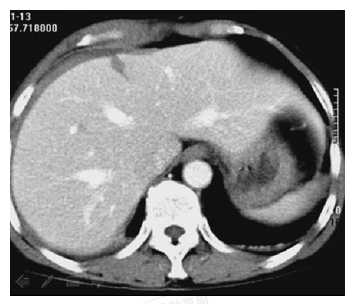

患者,女性,20歲。胸腹部被車(chē)撞傷5小時(shí)。診斷為

A.肝破裂

B.脾破裂

C.肝脾破裂

D.肝腎挫裂傷

E.腎損傷

【答案】A